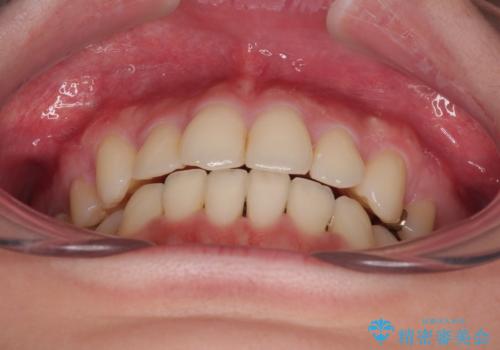

デコボコがスッキリするだけでなく、口元の突出感も少し改善され、満足のいく仕上がりとなりました。